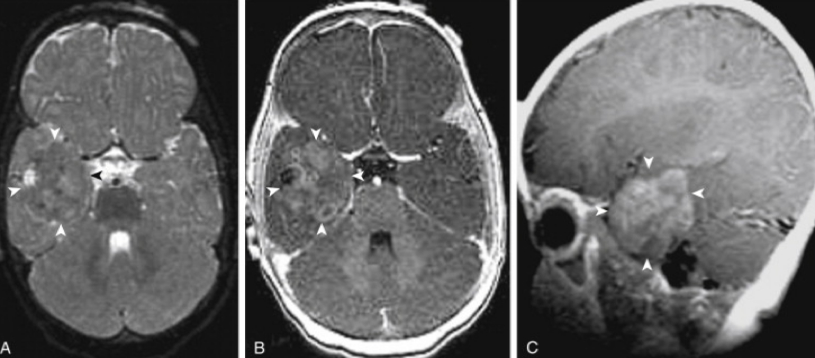

室管膜瘤是排列在脊髓中心和脑室的室管膜细胞的胶质肿瘤。在物理上是柔软的,呈灰色或红色,其可以发生在中枢神经系统任何有室管膜细胞存在的地方。常发生在儿童和成人,但在儿童中比成人更常见。

WHOII级:是常见的室管膜瘤。这个级别存在许多室管膜瘤亚型,包括细胞型、乳头型、伸长型、RELA融合阳性、透明细胞型室管膜瘤。其可能出现在脑室系统中产生脑脊液的任何地方。对于室管膜瘤二级是良性还是恶性?INC旗下组织国际神经外科顾问团成员、国际神经外科学院前主席、加拿大多伦多儿童医院神经外科主任James T.Rutka教授表示,2级室管膜瘤的几种亚型得到国际卫生组织的承认,大多数生长缓慢,属于良性肿瘤。对于Ⅱ级组织学室管膜瘤患者,据报道,5年和10年无进展生存率(Pfs)为80%-90%之间。[1]

WHOIII级:这些被称为间变性室管膜瘤,通常发生在颅骨、大脑和脑干,比其他级别的室管膜瘤生长更快,且有较强的浸润周围脑或扩散到脑脊液中的倾向。